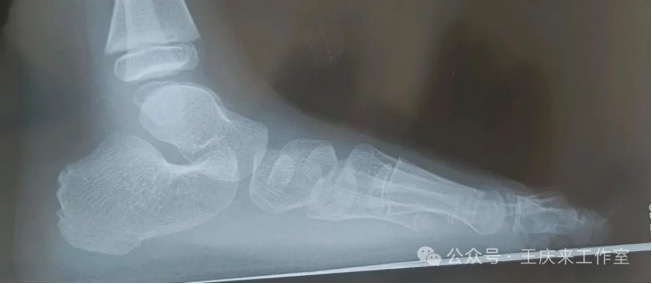

扁平足的检测方法主要有两种:足印法和影像学检查。足印法简单易行,通过观察足印最窄区与足长的比例,可以初步判断是否存在扁平足。影像学检查则更为精确,通过足部X线检查,可以测量足弓角度,明确足弓结构,从而准确判断是否存在扁平足。

门诊遇到一患者,女,15岁,学生,因“左踝及足疼痛1年余”,来我门诊就诊,询问病史患者1年前出现左踝及足疼痛,行走或起步时疼痛明显,休息后可见稍缓解。查体示双侧纵横足弓消失,左踝及足背轻微肿胀。根据症状体征,诊断为“扁平足”。